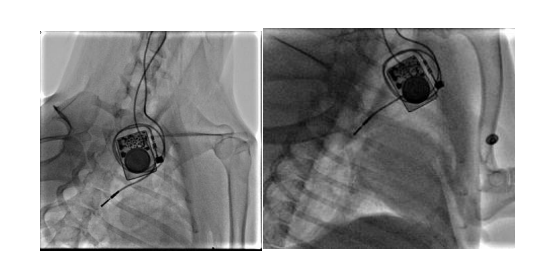

团队构建犬的慢性房颤动物模型,分析无创体表心电标测和有创心外膜心电标测系统采集的心电信号的相关性。我们通过经颈静脉介入(图10)和右外侧开胸小切口(图11)两种方法建立快速起搏右心房的犬慢性房颤模型

图9 经颈静脉介入路径构建右心房快速起博犬的慢性房颤模型

图10 经右侧胸部小切口构建右心房快速起搏犬的慢性房颤模型